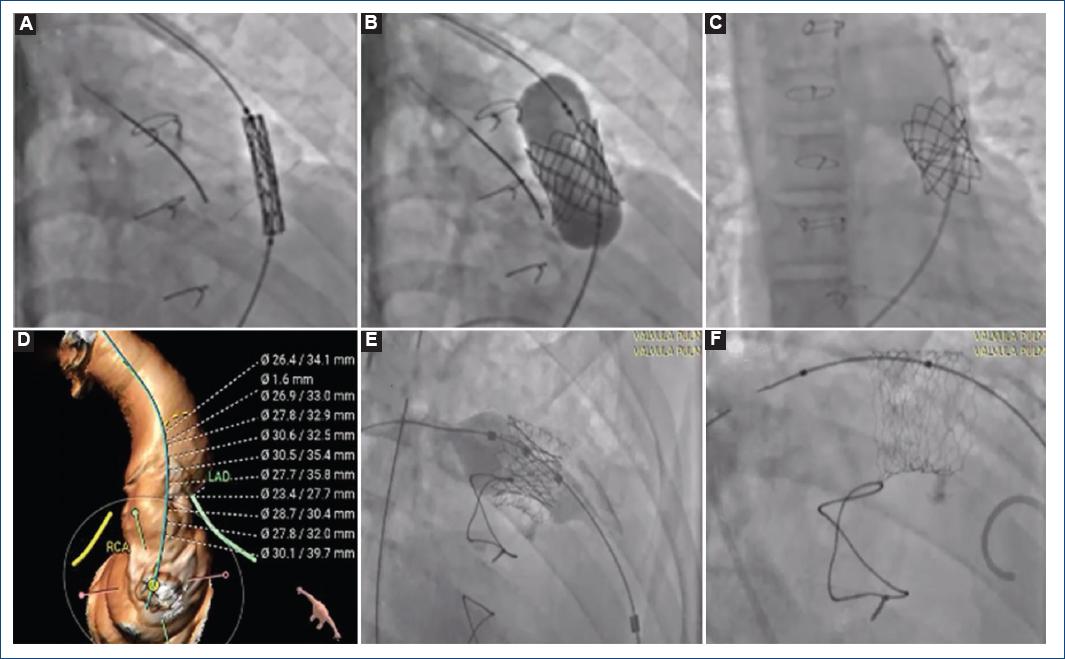

Paciente femenina de 13 años con diagnóstico de tetralogía de Fallot operada a los 8 años con implante de válvula biológica (Biocor Epic) en posición pulmonar, disfuncional a los 3-4 años (doble lesión: estenosis e insuficiencia severa). Fue llevada a cateterismo cardiaco para realización de valvuloplastia pulmonar (uso de balón Atlas Gold hasta 4 atm), hallazgo de gradiente pico a pico (por hemodinamia) > 60 mmHg y más de dos veces la presión del ventrículo derecho/izquierdo con reducción del 50% de la presión del ventrículo derecho frente al izquierdo y mejoría del gradiente en el TSVD a 16 mmHg tras la valvuloplastia. El ecocardiograma de control mostró la prótesis biológica en posición pulmonar con insuficiencia severa y estenosis moderada de predominio valvular, con gradiente máximo de 40 mmHg. Posteriormente se realizó el implante exitoso (válvula en válvula) de una válvula Melody TPV 22 (PB1018) Fr (Fig. 1).

Figura 1 Válvula Melody TPV 22 (PB1018) con Ensemble II 22 Fr implantada (válvula en válvula) en el caso 8. Descripción del procedimiento: se posiciona la válvula Melody a un tercio por debajo del plano de la válvula bioprotésica y el resto del stent por encima, se insufla el balón hasta 4 atm y se logra expandir de forma adecuada. La angiografía pulmonar en AP y LAO 90° confirma una válvula normofuncionante sin obstrucción. Presiones tras el implante: en la aorta 131/86/105 mmHg, en el ventrículo derecho 30/0/12 mmHg y en la arteria pulmonar 26/9/16 mmHg. A-C: angio TAC software 3-mensio (caso 10). D: Angio TAC software 3-mensio (caso 10). E y F: se implanta stent Andra® y luego válvula Myval No. 29 (caso 10).

Varón de 38 años con tetralogía de Fallot y ausencia de rama pulmonar izquierda con hipertensión pulmonar, intervenido quirúrgicamente en tres oportunidades, la última a los 14 años (homoinjerto en posición pulmonar), que mostró disfunción 18 años después, asociada a deterioro de la clase funcional (NYHA III/IV), condicionando falla cardiaca derecha e izquierda, por insuficiencia pulmonar libre, signos de sobrecarga sobre el ventrículo derecho e insuficiencia tricuspídea de grado IV/IV. El IPVP con una válvula Myval No. 30.5 fue infructuoso por diversas causas, con intentos de extracción no positivos, por lo que se tomó la decisión de dejar el implante en posición de vena cava inferior con función adecuada sin alterar el retorno venoso sistémico inferior, con posterior implante en el mismo tiempo de una válvula Myval No. 29 mm con sistema 14 Fr sobre un stent previamente posicionado en el TSVD, con datos tras el procedimiento de disminución de la dilatación del ventrículo derecho y de la regurgitación tricuspídea. El paciente falleció 2 meses después por un evento cerebrovascular.